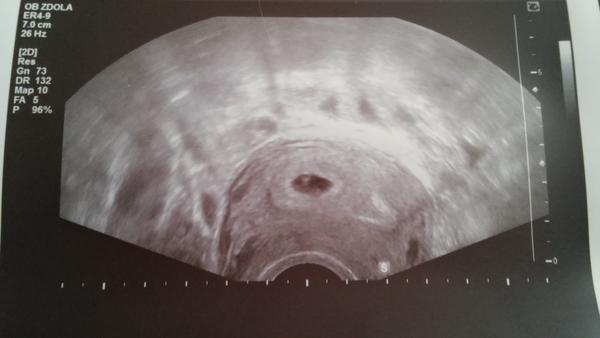

Ahoj,máte prosím někdo foto z utz od 5týdne?ted jsem 6+1tt tak mě zajímá,jak vypada váš utz,protože u mě na včerejší ko viz.foto 6+Ott díky

@jituli84 jak všude koukám na fotky,vidím ta takovou bublinku malinkou a já tam nemám vůbec nic.

@maminka2020 z ty fotky je vidět, ze jde o ně moc kvalitní Uz 🙂 takže rozhodně klid 🙂 je ještě dost casu na to, aby bylo něco pořádně vidět 🙂

@maminka2020 Tak já měla dva týdny zpět úplně stejný obrázek (prázdný gestační váček - 5. týden). Objednali mě moc brzy a dva týdny jsem se zbytečně stresovala. Min. týden jsem byla na kontrolním ultrazvuku a bylo tam krásně vidět i srdíčko. Prostě jsem měla ovulaci později. Držím pěsti, ať to dobře dopadne.